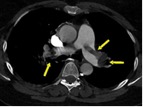

В статье представлен случай успешного хирургического лечения тромбоэмболии легочной артерии у пациентки с высоким риском ранней сердечной смерти на фоне парадоксальной эмболии, осложненной острым нарушением мозгового кровообращения. Криптогенное острое нарушение мозгового кровообращения в комбинации с тяжелой прогрессирующей правожелудочковой недостаточностью на фоне ТЭЛА обусловливает серьезные трудности при принятии решения в отношении тактики лечения у данных больных. Внутрисердечная локализация тромбоэмбола, угрожаемая развитием не только рецидива тромбоэмболии легочной артерии, но и парадоксальной эмболии требует незамедлительного выполнения комплекса дифференциально-диагностического обследования, направленного на верификацию патофизиологического механизма развития заболевания, что во многом определяет эффективность проводимого лечения. Анализ доступных литературных данных, приведенный в работе, а также анализ клинического случая позволяют выработать тактический алгоритм в этой группе пациентов и определить показания к открытому оперативному вмешательству.